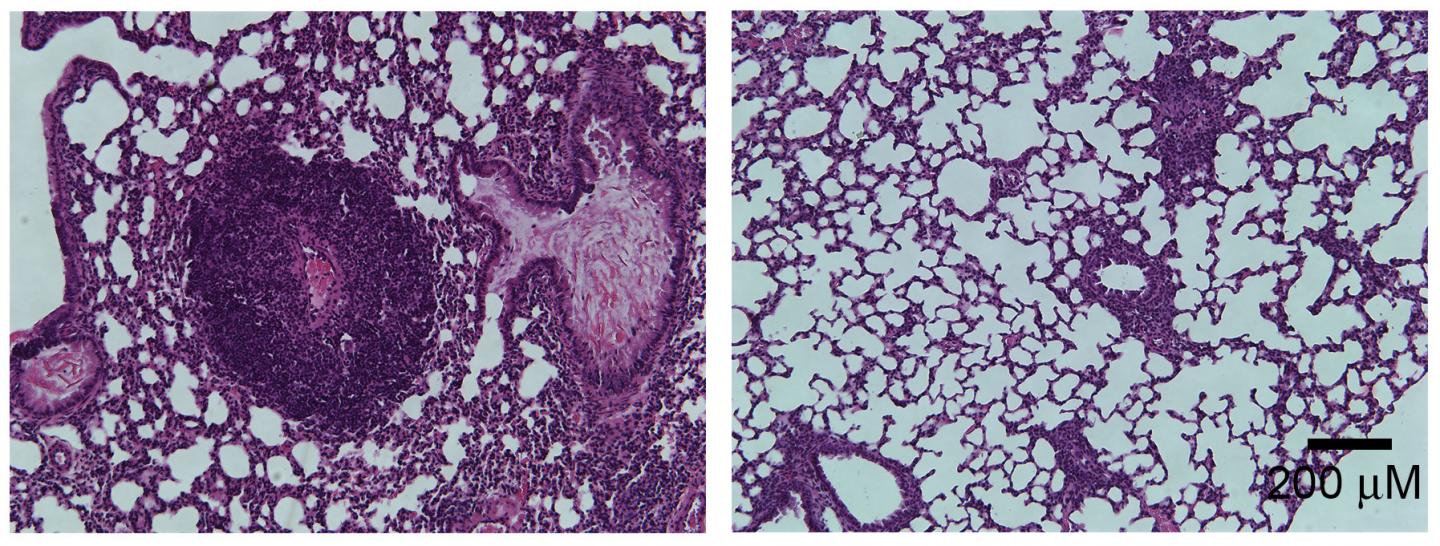

Autoimmune diseases can also be caused by changes in the gut microbiome, the population of bacteria that reside within the gastrointestinal tract. In the study, the team led by Yuying Liu and J. Marc Rhoads at The University of Texas Health Science Center at Houston McGovern Medical School find that mice carrying a mutant version of the Foxp3 gene show changes in their gut microbiome at around the same time that they develop autoimmune symptoms. In particular, the mice have lower levels of bacteria from the genus Lactobacillus . The researchers discovered that by feeding the mice with Lactobacillus reuteri , they could "reset" the gut bacterial community and reduce the levels of inflammation, significantly extending the animals' survival.